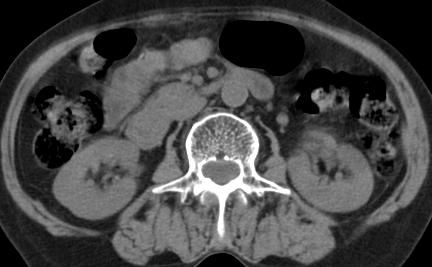

以下是引用齐原在2006-11-8 23:21:00的发言:[br]肝脏体积增大.肝表凸凹不平,肝内胆管扩张,胆总管扩张,胆总管末端突然截断,胰腺勾突增大,形态不规则.胰管扩张.考虑胰头癌.并低位梗阻性胆系扩张,胆囊炎.脾大.建议增强

以下是引用dyqct在2006-11-9 9:14:00的发言:[br]肝大,表面呈波浪状,肝内外胆管扩张,胆总管下端腔内见小结节状等密度影,胰管轻度扩张。胆囊显示不清。[br]考虑:1、胆总管下端占位性病变(等密度结石?壶腹部肿瘤?);[br] 2、肝硬化?[br] 3、建议增强扫描进一步检查。